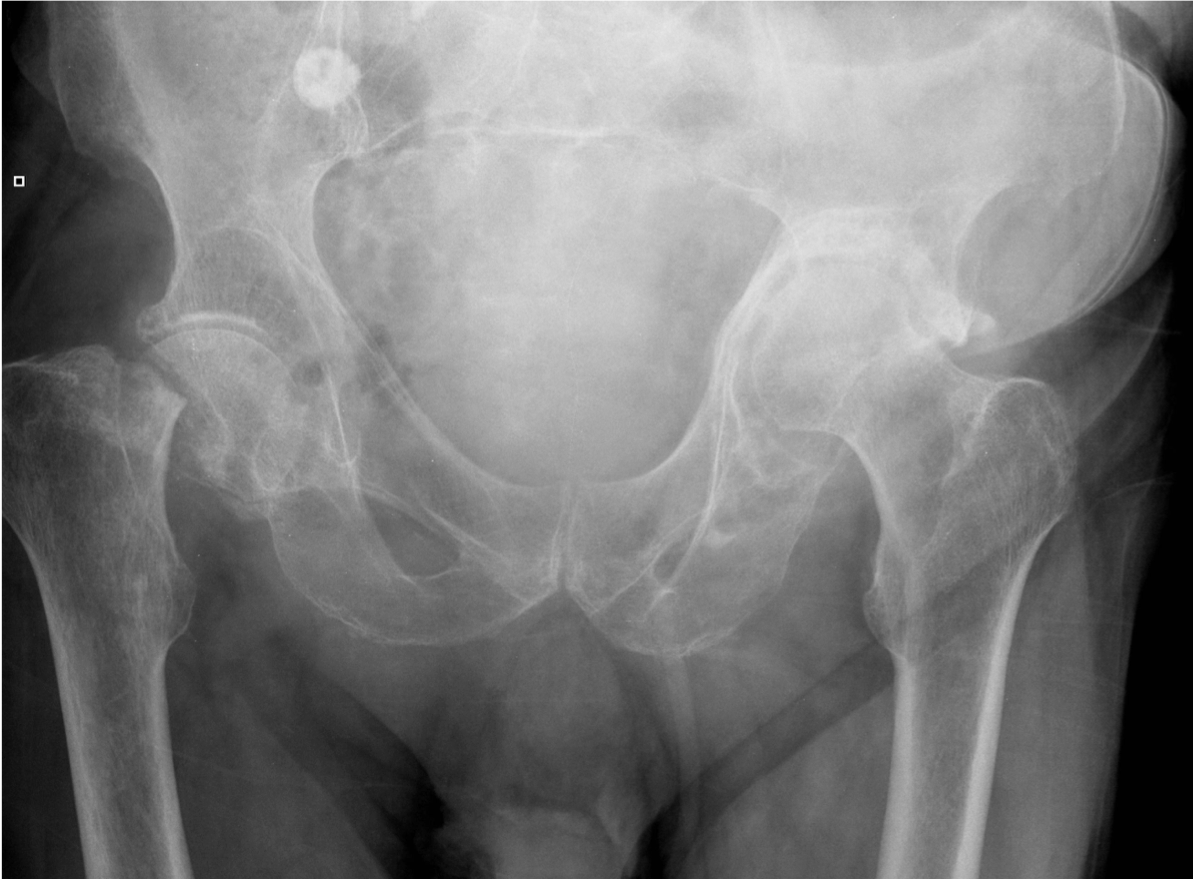

A 78 year old woman fell in her home. She could not get up again due to pain in her right groin. An ambulance was called.

An 48 year old man presented to the ED with 3-day history of left hip pain after falling in the shower. He was struggling to walk. On examination his left leg was a little shorter than the right and slightly laterally rotated.

What action would you take? Justify your course of action / investigation / management!